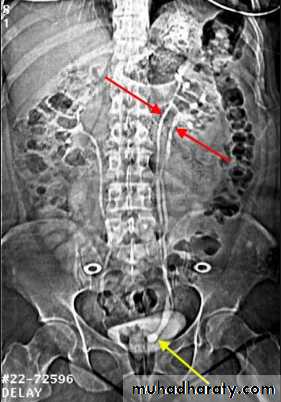

IVU

Large kidney .Lobulated out-line.

Distortion of pelvi- calyceal system depend on cyst size, number and position.

In advanced cases there is elongation and stretching of minor and major calyces ( spider leg).

In advanced cases IVU shows non-functioning kidney .